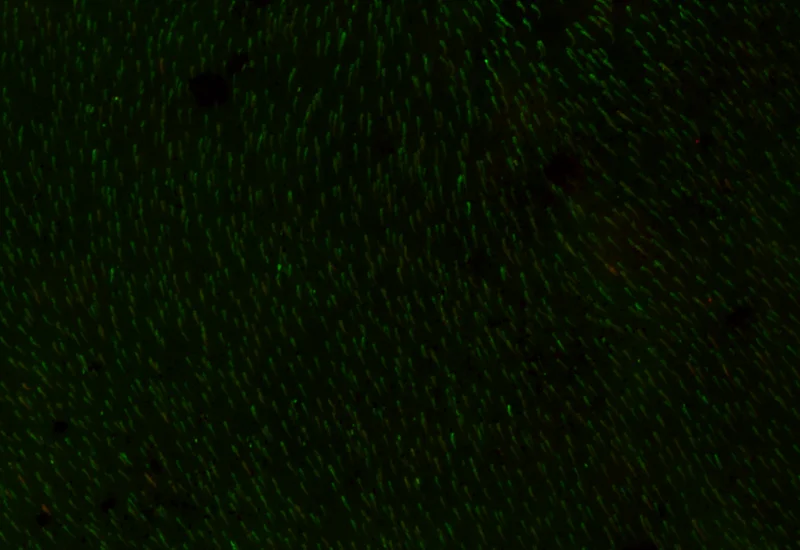

Original Image

Rods and Cones detection

The IF Rods & Cones in Retina App detects the rods and cones based on specific staining. It outputs the number, density and length of detected structures as well as the number, percentage and density of marker-stained rods and cones.